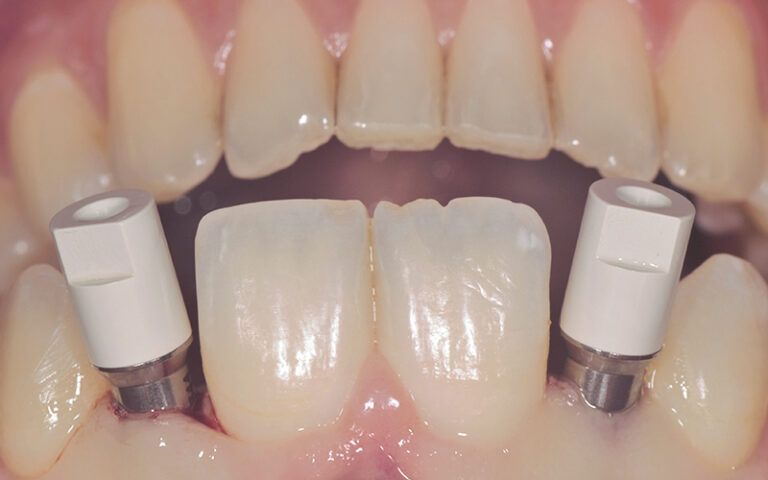

After three months of osseointegration, the second surgery performed on both implants and the digital impressions were taken with the TRIOS (3Shape) intraoral scanner.

Details of the digital impression with the scan abutments placed in the mouth Details of the digital impression with the scan abutments placed in the mouth Details of the digital impression with the scan abutments placed in the mouth

The impressions were sent to a reliable prosthetics laboratory to make provisionals while they worked on the CAD-CAM design and manufacture of the definitive zirconium crowns.